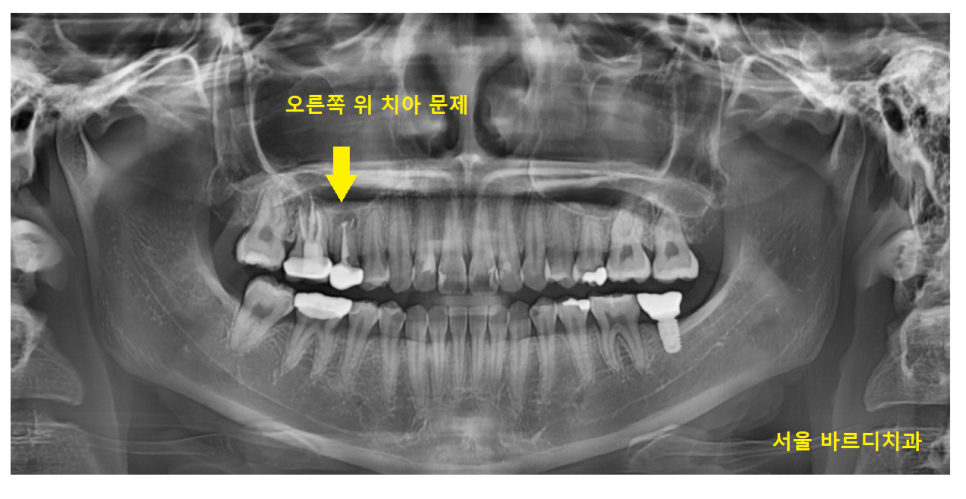

해당 환자분은 오른쪽 위에 치아로

오랜 시간 고통받았다고 하셨습니다.

뿌리 끝을 잘라내는 수술만 두번을 받았다고 하셔서

엑스레이를 찍어보았습니다.

옆에 치아와 확연하게 다른 것이 보이네요~